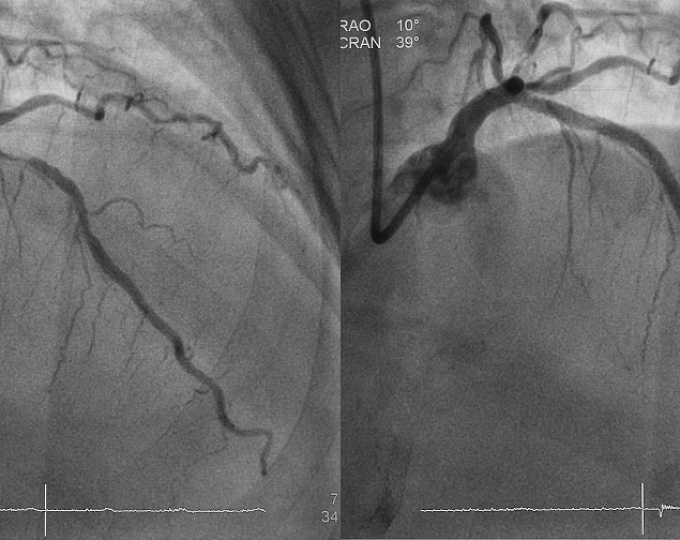

Лучевой или бедренный доступ при ЧКВ в случае ИМспST?

Чрескожное вмешательство на коронарных артериях (ЧКВ) является наиболее эффективным методом реперфузии у пациентов с инфарктом миокарда с подъемом сегмента ST (ИМспST).

Изначально ЧКВ выполнялось с использованием бедренного доступа, однако в последнее время все чаще используется доступ через лучевую артерию, что объясняется его большей безопасностью, особенно при плановых вмешательствах. Однако сравнения лучевого и бедренного доступа в острых ситуациях (ИМспST) оказывались достаточно неопределенными. В связи с чем целью исследования SAFAR-STEMI стала оценка эффективности и безопасности лучевого и бедренного доступа при ЧКВ в случае ИМспST.

• В исследование было включено 2292 пациента, из них первичное ЧКВ лучевым доступом было выполнено 1082 пациентам, тогда как бедренным – 1109.

• Частота наступления смерти от всех причин за 30-дневный период составила 1.5% в группе лучевого доступа и 1.3% – в группе бедренного (относительный риск 1.15; 95% доверительный интервал 0.58-2.30; p=0.69).

• Частота повторных инфарктов, инсультов и кровотечений также не отличалась между двумя группами.

Результаты представленного исследования продемонстрировали отсутствие различий между лучевым и бедренным доступом при ИМспST относительно частоты наступления смертельных исходов в 30-дневный период. По-видимому, оба подхода следует считать правомерным, а определяющим фактором в выборе доступа для реваскуляризации должен быть опыт хирурга.